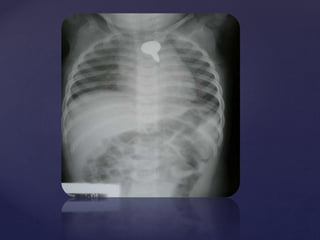

 Plain X Ray neck ,

chest and abdomen

AP view.

 Showing a round

radio opaque foreign

body in the

esophagus.

 Probably a coin.

Fig 2

 Plain X Ray neck

Lateral view.

 Showing edge on

view in lateral view

suggesting of FB in

oesophagus (in

contrast to FB

trachea)